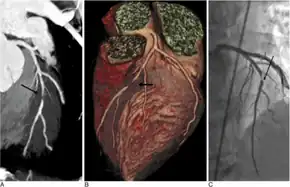

| Diagnostic method | Electrocardiogram, cardiac stress test, coronary computed tomographic angiography, coronary angiogram[8] |

Risk factors include high blood pressure, smoking, diabetes, lack of exercise, obesity, high blood cholesterol, poor diet, depression, and excessive alcohol.[6][7][17] A number of tests may help with diagnoses including: electrocardiogram, cardiac stress testing, coronary computed tomographic angiography, and coronary angiogram, among others.[8]